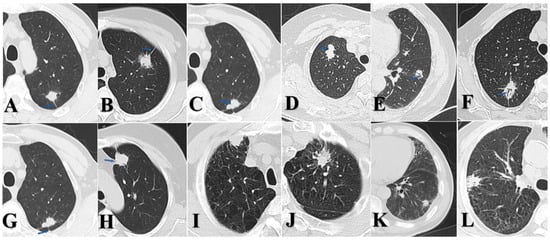

Two board-certified radiologists blinded to pathological results independently assessed the consolidation tumor ratio (CTR) for each case. Based on CTR values, all lesions were categorized as follows: solid nodules (SDNs, CTR = 100%), mixed ground-glass nodules (mGGNs, CTR ≥ 50%), and mGGNs CTR < 50%. Both radiologists independently extracted the following imaging features (Figure 1): spicular sign, lobulation sign, air bronchogram, pleural indentation, pulmonary emphysema, and interstitial pneumonia. Final determinations were reached through consensus in cases of disagreement.

Figure 1. (A) p-LUSC, male, spicular sign. (B) p-LUAD, female, spicular sign. (C) p-LUSC, male, lobulation sign. (D) p-LUAD, female, lobulation sign. (E) p-LUSC, male, air bronchogram. (F) p-LUAD, female, air bronchogram. (G) p-LUSC, male, pleural indentation. (H) p-LUAD, female, pleural indentation. (I) p-LUSC, male, emphysema. (J) p-LUAD, male, emphysema. (K) p-LUSC, male, interstitial pneumonia. (L) p-LUAD, male, interstitial pneumonia.

Our subgroup analysis—stratified by tumor size and CTR—revealed that >2.0 to ≤3.0 cm SDNs of p-LUAD demonstrated significantly greater malignant invasion than both 0–2.0 cm SDNs of p-LUAD and >2.0 to ≤3.0 cm p-LUSC. Notably, no statistically significant difference in lymph node metastasis was observed between >2.0 and ≤3.0 cm and 0–2.0 cm p-LUSC cases, which is consistent with the established literature [10,34]. Our study revealed that p-LUSC exhibits a distinct behavior: it rarely presents as GGNs, and the malignant aggressiveness does not increase with a tumor diameter up to 3 cm. Of note, in the 0–2.0 cm subgroup, p-LUSC and SDNs of p-LUAD showed no statistically significant differences in lymph node metastasis and lymphovascular invasion; however, p-LUAD demonstrated greater aggressiveness in terms of pleural invasion. In the >2.0 to ≤3.0 cm subgroup, SDNs of p-LUAD exhibited a more pronounced propensity for pleural invasion, whereas p-LUSC did not. This observation is consistent with previous reports; meanwhile, LUAD appears to have a propensity for pleural seeding after invading the pleura [35,36,37,38]. Even when pleural invasion occurs, LUSC tends to directly invade the chest wall rather than cause extensive pleural seeding metastasis or malignant pleural effusion [39,40]. Figure 1I demonstrates a preoperative CT scan of a patient with p-LUSC at our institution, revealing a mass located in the right upper lobe of the lung, abutting the pleura, with manifestations of pleural thickening, pleural involvement, without signs of pleural dissemination, malignant pleural effusion, or distant metastasis. Postoperative pathology confirmed visceral pleural invasion and desmoplastic reaction. This suggests that p-LUSC, when invading the pleura, is often accompanied by desmoplastic reaction, which leads to a tendency for local invasion rather than distant dissemination. These clinically relevant characteristics of early-stage p-LUSC have been underemphasized in the previous literature, despite its significant implications for clinical management.